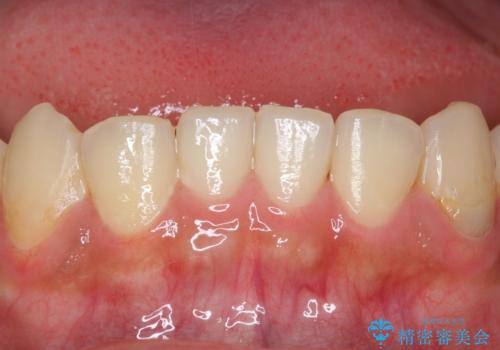

精査したところ、ほとんどの歯が保険内のレジンで充填されており、咬み合わせも悪く咬合していない歯もありました。

虫歯をしっかりと治療したのち、オールセラミッククラウンによる補綴治療を行いました。

下顎の埋伏していた親知らずも抜去しました。